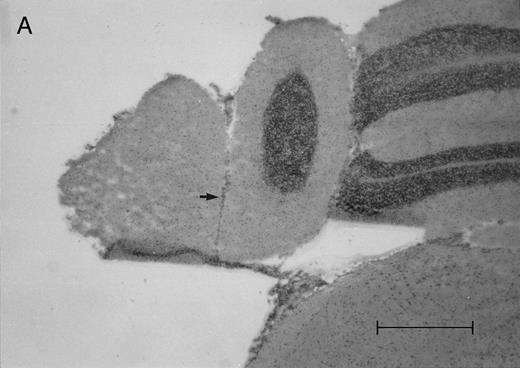

Histologic progression of leukemic meningitis. All sections are 12-μm coronal sections. (A) Cisterna magna at 14 days postinjection showing a small cluster of HPB-ALL cells (arrow) in the subarachnoid space, H&E, bar = 0.64 mm. (B) Cisterna magna at 21 days postinjection showing large groups of HPB-ALL cells in the subarachnoid space (arrow), H&E, bar = 0.64 mm. Compare the large groups of cells shown here with the small cluster at 14 days postinjection shown in (A).

In the timed histologic study, animals were killed sequentially postintrathecal HPB-ALL cell injection. Three animals each at 1, 2, 4, 7, 11, 14, and 19 days, two animals at 20 days, and seven animals at 21 days postinjection underwent CSF sampling and were immediately killed. At the 19 day time point, only CSF was sampled, as the same group of animals was also sampled and then killed as part of the 21 day time point. On histologic examination, brain sections from animals killed between 1 and 11 days postinjection showed rare, dispersed leukemic cells in the subarachnoid space at both the cerebral and cerebellar levels. At day 14, very small clusters of HPB-ALL cells could be observed in the subarachnoid space at the cerebellar level in two of three animals (Fig 2A). By 21 days postinjection, large groups of cells could be seen in the subarachnoid space of all animals in the cerebellar sections (Fig 2B). Collections of leukemic cells were concentrated in the most posterior cerebellar sections, in the meninges of the cisterna magna. Small clusters of leukemic cells or scattered leukemic cells were observed in the subarachnoid space of cerebral sections (Fig 2C and D). In animals that developed symptoms during the course of the natural progression of leukemic meningitis, there was extensive infiltration of the subarachnoid space by leukemic cells throughout the brain, with the most dense involvement in the basal region. This was accompanied by permeation of the Virchow-Robin spaces (Fig 2E). The pattern was strikingly similar to leukemic meningitis in humans.